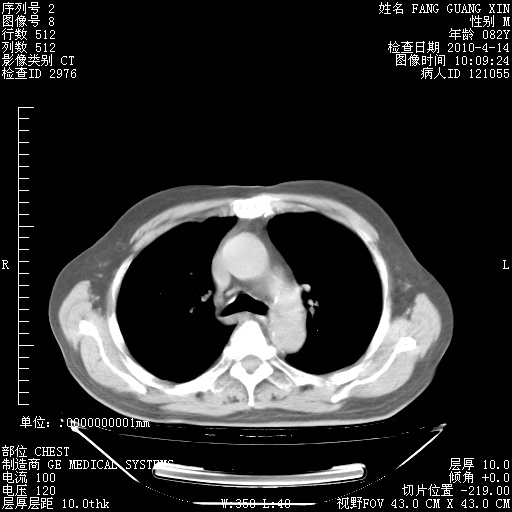

4月14日肺部CT

23.JPG

24.JPG

25.JPG

26.JPG